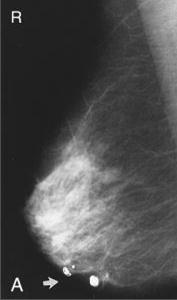

Καλοήθεις αποτιτανώσεις (εικόνα Α)

Δερματικού τύπου (είναι στρογγυλές)

Αγγειακού τύπου (είναι γραμμοειδείς tram track-line)

Δυστροφικού τύπου (αναπτύσσονται σε ουλώδη ιστό)

Εκκριτικού τύπου (αναπτύσσονται κατά μήκος των πόρων, είναι κυλινδρικές)

Λοβιακού τύπου (εντός της τελικής ανατομικής δομής του βοτρυδίου, είναι στρογγυλές, ελλειψοειδείς, ίσως σχηματίζουν ομάδες, μπορεί να είναι διάσπαρτες ή συρρέουσες)

Είναι λεπτές, πλειόμορφες, ανομοιογενείς ως προς την πυκνότητά τους και το σχήμα τους.